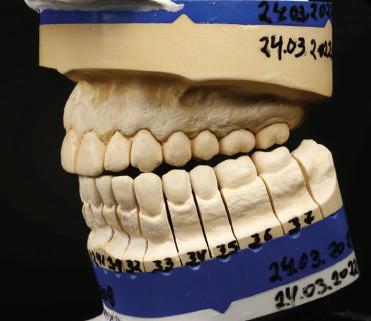

20 Dental Tribune Bulgarian Edition / октомври 2022 г. П ациентите със завършен растеж и скелетни проблеми обикновено представляват предизвикателство за ортодонт ската практика. Необходимостта от изваждане на зъби в комбинация с особеностите на възрастовата ортодонтия изисква особено внима ние. Фокусът върху критично важното значение на позицията на долните резци във връзка с дългосроч ната стабилност и постигането на оптимални оклузални взаимоотношения при затварянето на екстракционните пространства лесно може да излезе извън контрол. Когато към тези чисто кли нични проблеми се добави и стресът от натоваре ната практика, предизвикателството става още по-голямо. Всички тези фактори налагат използ ването на доказан подход с ясни и последовател ни стъпки, в което се разкрива силата на дисциплината „Алекзандър“ – предвидим протокол през целия процес на елиминиране на ротациите, ниве лиране на дъгите, затваряне на екстракционните пространства и финализиране на случая. Именно такъв е и случаят, който презентираме –екстракционен, скелетен клас 3 при възрастен па циент, лекуван по системата „Алекзандър“. ПРЕДВИДИМИ РЕЗУЛТАТИ ПРИ ПАЦИЕНТИ СЪС ЗАВЪРШЕН РАСТЕЖ И СКЕЛЕТЕН КЛАС 3, ИЗПОЛЗВАЙКИ ЕКСТРАКЦИОННО ЛЕЧЕНИЕ ПО ДИСЦИПЛИНАТА „АЛЕКЗАНДЪР“ Д-р Радой Димитров, България Преди започване на лечение клиничен случай | ортодонтия Фиг. 1а–1e Преди започване на лечение. Пациентът пристига в практиката с основното оплакване от невъзмож ност за нормално дъвчене. Снета е цялата необходима диагностична ин формация. Фиг. 1f–1h Снимки в профил и анфас. Фиг. 1i–1k Панорамна снимка, телерентгенография и анализ на телерент генография. Фиг. 1а Фиг. 1d Фиг. 1f Фиг. 1g Фиг. 1h Фиг. 1e Фиг. 1b Фиг. 1c Фиг. 1i Фиг. 1j Фиг. 1k

closed.

21Dental Tribune Bulgarian Edition / октомври 2022 г. ДИАГНОСТИЧНИ РЕЗУЛТАТИ: 1. Възраст на пациента: 21 години 2. Скелетен клас III (ANB 0) 3. Зъбен клас 3 4. Ръбцова захапка във фронта, кръстосана в дисталните участъци 5. Тясна горна челюст 6. Overjet – 0 мм, Overbite – 0 мм 7. Несъответствие на горната с долната средна линия 8. Единични контакти в ЦО 9. Хиподивергентен тип на растеж SN/MP – 33.5 10. Неравен гингивален контур 11. Неравна линия на усмивката 12. Тенденция за рецесии в долен фронт ПРЕПОРЪЧИТЕЛНО ЛЕЧЕНИЕ: Пълно ортодонтско лечение с метални брекети „Алекзандър“ Корекция на клас 3 захапката в областта на кучешките зъби с екстракция на първите пре молари в долна челюст Корекция на кръстосаната захапка в дистални участъци Коригиране на ръбцовата захапка във фронта Подобряване на ОJ и OB на пациента Стрипинг в долен фронт Подреждане на зъбите в горната и долната челюст Професионално хигиенизиране и профилактични дентални прегледи са препоръчителни на всеки 6 месеца. 1-ви месец След 1 месец са залепени брекети в горната челюст – поставена е еластична дъга. 016 NiTi. В долната челюст са елиминирани ротациите, поставена е стоманена дъга. 016SS, закалена с ток, и еластична верижка за затваряне на пространствата. 3-ти месец В долната челюст е поставена трета дъга – 17 x 25 NiTi с къси лигатури и верижка

В горната челюст се затварят пространствата с дъга .016SS и верижка. 5-и месец На 5-ия месец след залепяне на брекетите в долната челюст е поставена стоманена дъга 16 x 22 SS с четвъртито сечение, омега луп и тай бек. В горната челюст е поставена дъга 17 x 25 NiTi. Поради липсата на стабилни оклузални контакти са поставени лингвални верижки в областта на моларите, за да се предотврати нежелана ротация на 7-ите зъби. 6-и месец На 6-ия месец от началото на лечението са екстрахирани долните първи премолари, поставена е дъга 16 x 22 SS със затваряща чупка teardrop. Чупката се активира всеки месец по 1 мм с чинч-бек. клиничен случай | ортодонтия СТЪПКИ НА ЛЕЧЕНИЕТО Начало на лечението Лечението започва с поставяне на апарат за бърза експанзия в горната челюст. През първия месец от лечението са направени 24 оборота на апарата за експанзия. Залепени са брекети в долната челюст, поставена е дъга 17x25 CuNiTi, като са предпи сани клас 3 ластици (1/4”,4 1/2 oz) по време на сън, за да се осигури контрол върху торка на долните резци. Фиг. 2а Фиг. 3a Фиг. 4a Фиг. 3b Фиг. 4b Фиг. 3c Фиг. 4c Фиг. 3d Фиг. 4d Фиг. 3e Фиг. 4e Фиг. 5a Фиг. 5b Фиг. 5c Фиг. 5d Фиг. 5e Фиг. 6a Фиг. 6b Фиг. 6c Фиг. 6d Фиг. 6e Фиг. 7a Фиг. 7b Фиг. 7c Фиг. 7d Фиг. 7e Фиг. 2b Фиг. 2c Фиг. 2d

Dental Tribune Bulgarian Edition / октомври 2022 г.22 клиничен случай | ортодонтия 14-и месец В горната и долната челюст са поставени последни стоманени дъга с омега луп и тай бек – 17 x 25 SS с четвъртито сечение. Назначени е ластик за средната линия в комбинация с клас 3 ластик (1/4”, 6 1/2 oz). Контролни рентгенографии 13-и месец Екстракционните пространства са затворени. Направена е контролна панорамна снимка за оценка позицията на корените. Взето е решение за презалепване на брекетите на 12, 22 и пръстените на 36 и 46. 21-ви месец Средната линия в горната и долната челюст съвпадат. Ластиците са спрени. Свалени са пръстените и брекетите в горната и долната челюст, зигзаг ластици не са използвани поради благоприятните оклузални взаимоотношения. Фиг. 11j Ортопантомография в края на лечението. Фиг. 11k Телерентгенография след края на лечението. Фиг. 11l Анализ на телерентгенографията след лечението. Фиг. 11m Последователност на дъгите в горната и долната челюст Фиг. 11n Суперимпозиция на PreOp и PostOp ортопантомографии. 10-и месец Затварянето на пространствата е предвидимо и контролирано, без да се отварят пространства в зъбната дъга. Фиг. 8a Фиг. 8b Фиг. 8c Фиг. 8d Фиг. 8e Фиг. 10a Фиг. 10b Фиг. 10c Фиг. 10d Фиг. 10e Фиг. 9a Фиг. 9b Фиг. 9c Фиг. 9d Фиг. 9e Фиг. 9f Фиг. 11a Фиг. 11f Фиг. 11j Фиг. 11l Фиг. 11m Фиг. 11n Фиг. 11k Фиг. 11g Фиг. 11h Фиг. 11i Фиг. 11b Фиг. 11c Фиг. 11d Фиг. 11e

Dental Tribune Bulgarian Edition / октомври 2022 г. 23клиничен случай | ортодонтия реклама Лечението е продължило 21 месеца. Проведено е домашно избелване с индивидуални шини. За автора: Д-р Радой Димитров завършва с отличие Факултета по дентална медицина към МУ–София през 2015 г. В продължение на 5 години работи в няколко водещи практики в София, като през 2019 г. заедно със своята съпру га д-р Траяна Димитрова основават собствена практика в гр. Гоце Делчев –Dimitrovi Dental Care. Посещава редица курсове за повишаване на квалификаци ята, но най-сериозен тласък в развитието на ортодонтската си практика получава след завършването на комплексната ортодонтска програма, воде на от д-р Иван Горялов, базирана на дисциплината „Алекзандър“ – система с повече от 50 години опит в целия свят. Д-р Димитров е член на Българския изследователски клуб „Алекзандър“. Взе ма участие като гост-лектор в симпозиума с международно участие The Power of the Alexander Discipline, който се проведе на 14–15.05.2022 г. С д-р Ди митров можете да свържете на тел. +359885 252 025. Заключение Представеният случай е ярък пример за възможностите и красо тата на дисциплината „Алекзандър“ – приложен е утвърден под ход с ясни правила и са постигнати очакваните цели. Резулта тът ще бъде дългосрочно стабилен, тъй като са спазени всички правила, които се отнасят към максимално комфортната пози ция на зъбите в края на лечението. Постигнати са красива усмив ка и стабилна оклузия. ПОСТИГНАТИ РЕЗУЛТАТИ ОТ ЛЕЧЕНИЕТО 1. Коригирана ръбцова захапка 2. Коригирана клас 3 захапка в областта на ку чешките зъби 3. Коригирана кръстосана захапка в дисталните участъци 4. Коригиран овърджет и овърбайт 5. Разширена е горната зъбна дъга 6. Подредени зъби в горната и долната челюст 7. Постигната е стабилна захапка с множество контакти в ЦО 8. Драматично е подобрена дъвкателната функ ция 9. Подобрена е линията на усмивката ДРУГИ ПРОВЕДЕНИ ДЕНТАЛНИ ПРОЦЕДУРИ 1. Домашно избелване на зъбите 2. Екстракция на мъдреците Фиг. 12a Фиг. 12b Фиг. 12c Фиг. 12eФиг. 12d Фиг. 12f Фиг. 12g Информация за дати, цени и отстъпки www.bracescourses.com 0889 22 55 01 Практически курсове лектор д-р Иван Горялов Дисциплината „Алекзандър“ ПЪТЯТ КЪМ СУПЕРУСМИВКИТЕ 100% връщане на цялата сума, ако не сте удовлетворени след преминаване на Ниво 1 Директно и индиректно залепяне на брекети Анализ, диагноза и план на лечение Лечение на клас 2 дълбока захапка Екстракционно лечение Лечение на клас 3 отворена захапка НИВО 5НИВО 1 НИВО 2 НИВО 3 НИВО 4